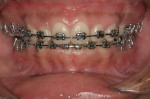

After Orthodontic Setup - Presurgical